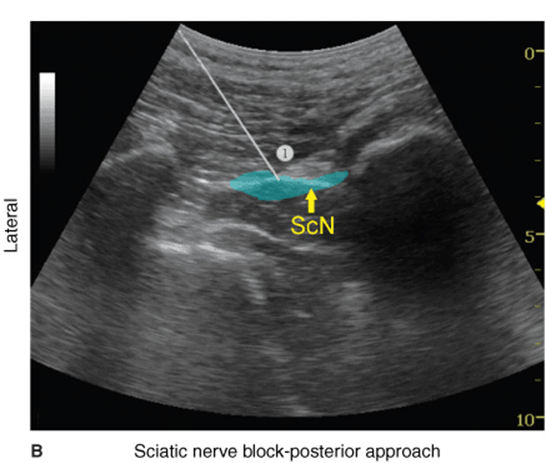

The description of the technique in this chapter will focus primarily on the transgluteal approach. However, since the subgluteal approach is performed just a few centimeters more distal and it is technically easier, the reader can easily perform either approach by using general guidelines provided and referring to Figure 39.2-3, Figure 39.2-4, and algorithms at the end of the chapter. With the patient in the described position, the skin is disinfected and the transducer is positioned so as to identify the sciatic nerve (Figure 39.2-4). If the nerve is not immediately apparent, tilting the transducer proximally or distally can help improve the contrast and bring the nerve “out” of the background of the musculature. Often, the nerve is much better imaged after the injection of local anesthetic (Figure 39.2-5). Alternatively, sliding the transducer slightly proximally or distally can improve the quality of the image and allow for better visualization. Once identified, the needle is inserted in-plane, typically from the lateral aspect of the transducer and advanced toward the sciatic nerve. If nerve stimulation is used (1.0 mA, 0.1 msec), the passage of the needle through the anterior fascial plane of the gluteus muscles often is associated with a motor response of the calf or foot. Once the needle tip is positioned adjacent to the nerve (Figure 39.2-6A) and after careful aspiration to rule out an intravascular needle placement, 1 to 2 mL of local anesthetic is injected to document the proper injection site. Such injection often displaces the sciatic nerve away from the needle; therefore, an additional advancement of the needle 1 to 2 mm toward the nerve may be necessary to ensure the proper spread of the local anesthetic. When injection of the local anesthetic does not appear to result in a spread around the sciatic nerve, additional needle repositions and injections may be necessary. Assuring the absence of high resistance to injection is of utmost importance because the needle tip is difficult to visualize on ultrasound due to the steep angle and depth of the needle placement.

FIGURE 39.2-6. (A) Ultrasound image demonstrating the simulated needle path to reach the sciatic nerve (ScN) using an in-plane technique in transgluteal approach. The simulated needle (1) is shown transversing the gluteus muscle with its tip positioned at the lateral aspect of the sciatic nerve. (B) Needle path and distribution of local anesthetic (blue shaded area) to block the ScN through the transgluteal approach.

In an adult patient, 15 to 20 mL of local anesthetic is usually adequate for successful blockade of sciatic nerve (Figure 39.2-6). Although a single injection of such volumes of local anesthetic suffices, it may be beneficial to inject two to three smaller aliquots at different locations to ensure the spread of the local anesthetic solution around the sciatic nerve. The block dynamics and perioperative management are similar to those described in Chapter 19.